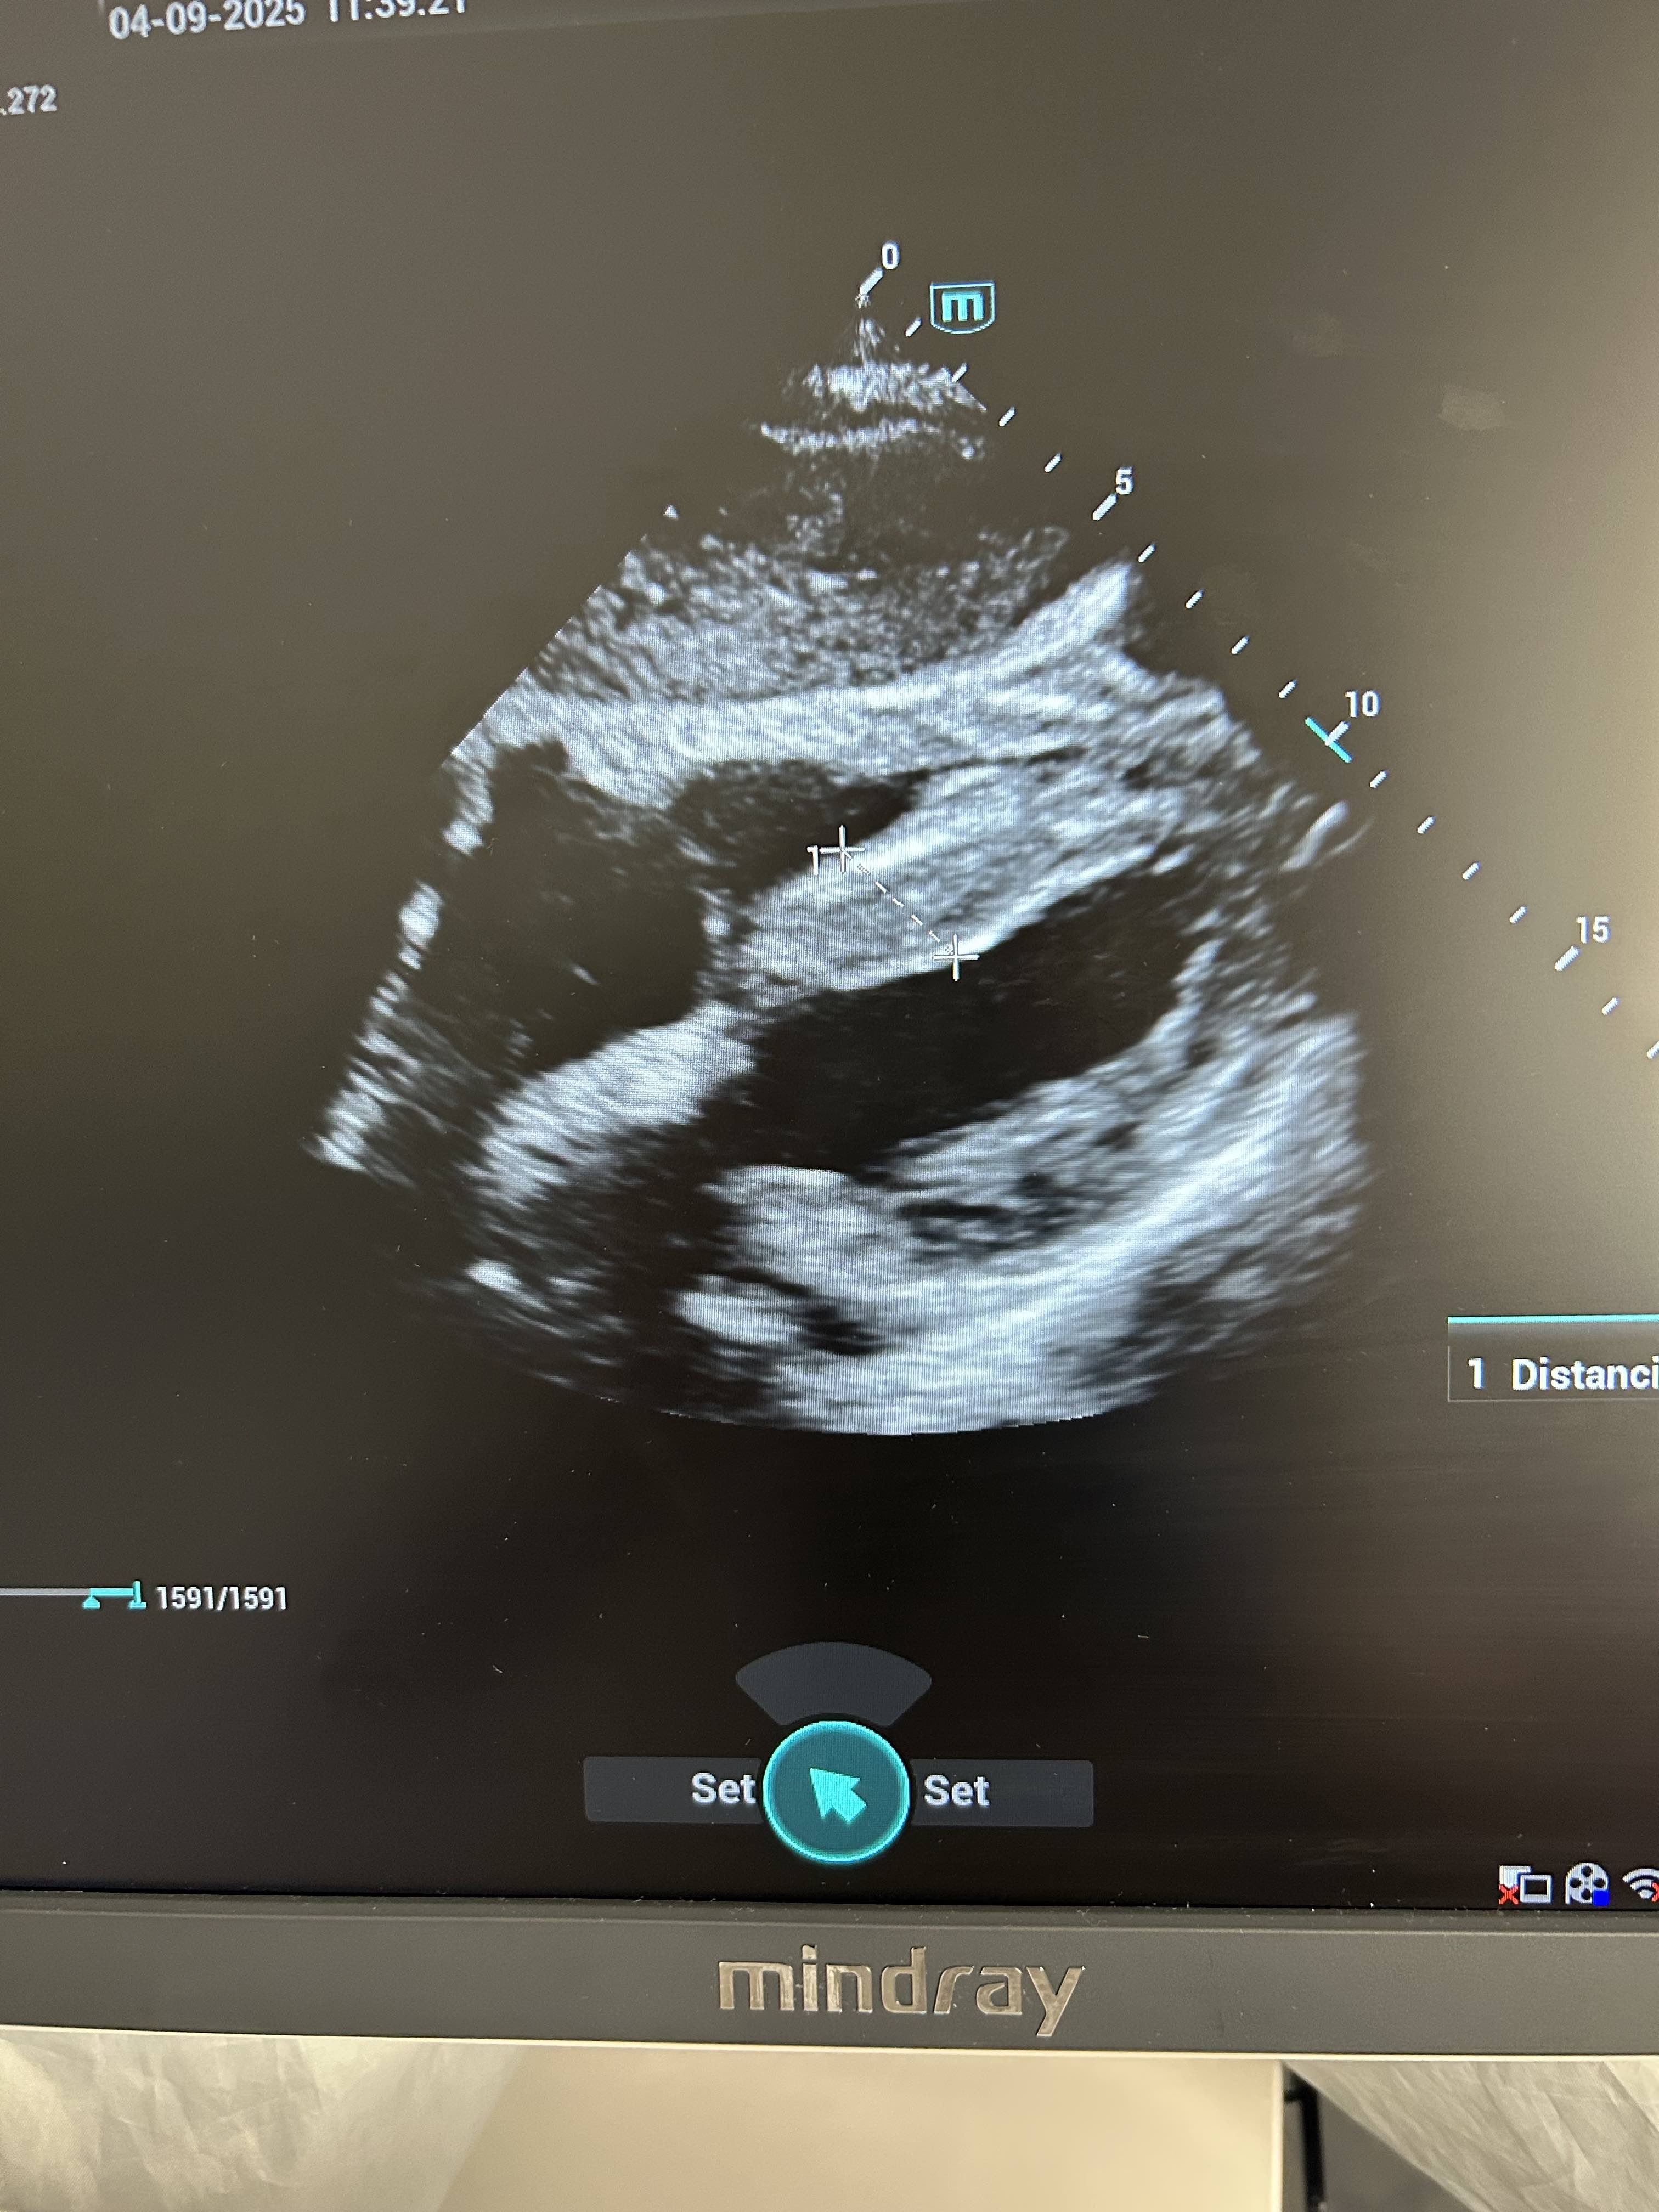

Hallazgos ecográficos

Al tratarse de un paciente con factores de riesgo cardiovascular decidimos realizar ecografía cardíaca; en la cual se visualiza una FEVI aparentemente preservada. Hipertrofia del septo con colapso de ventriculo derecho, bastante llamativa en una ventana de cuatro cámaras.